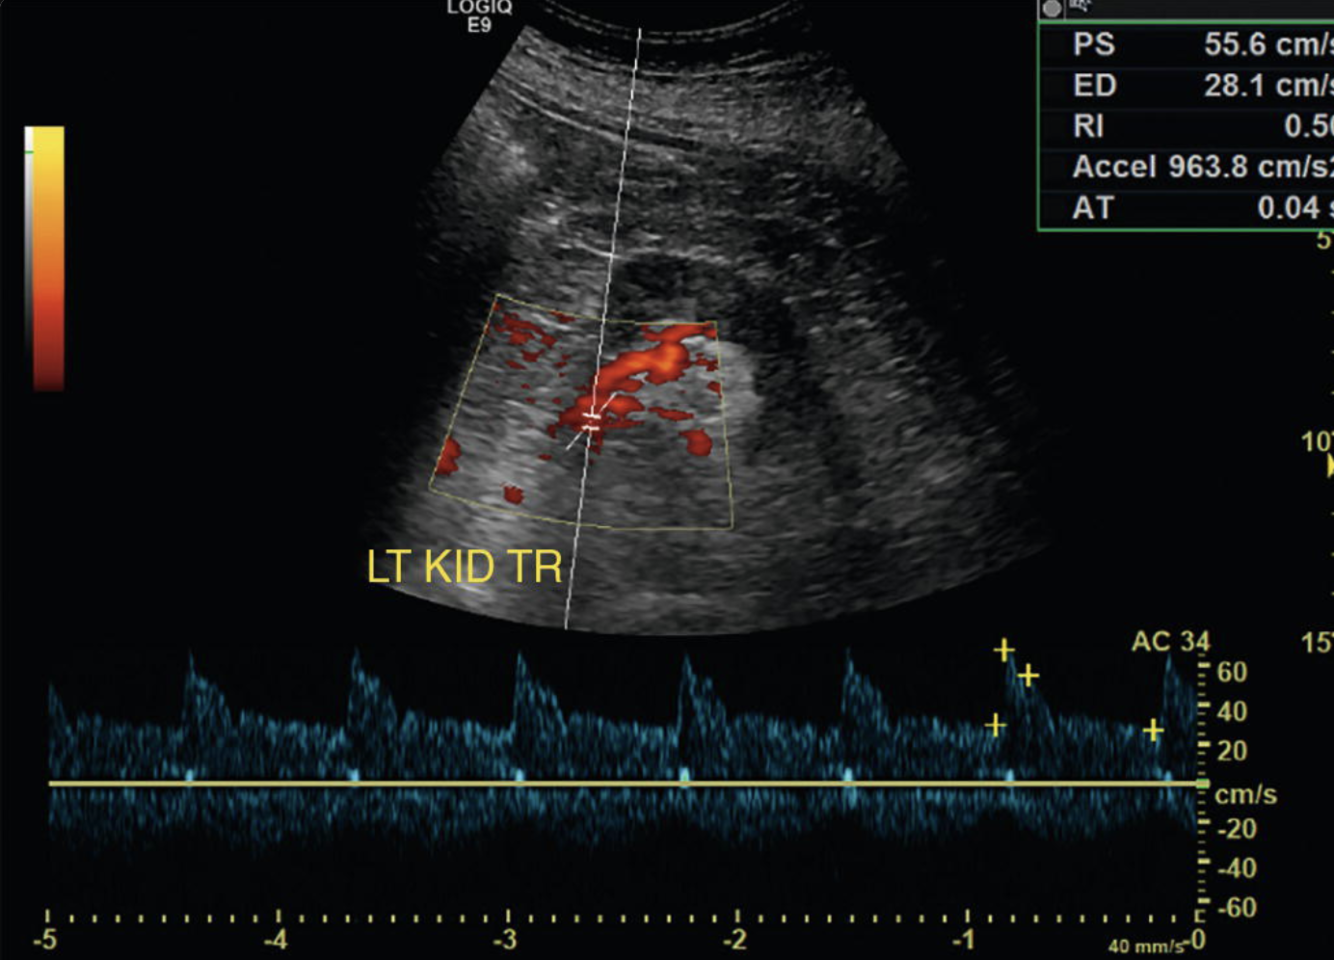

Why is CEUS useful for RCC diagnoses?